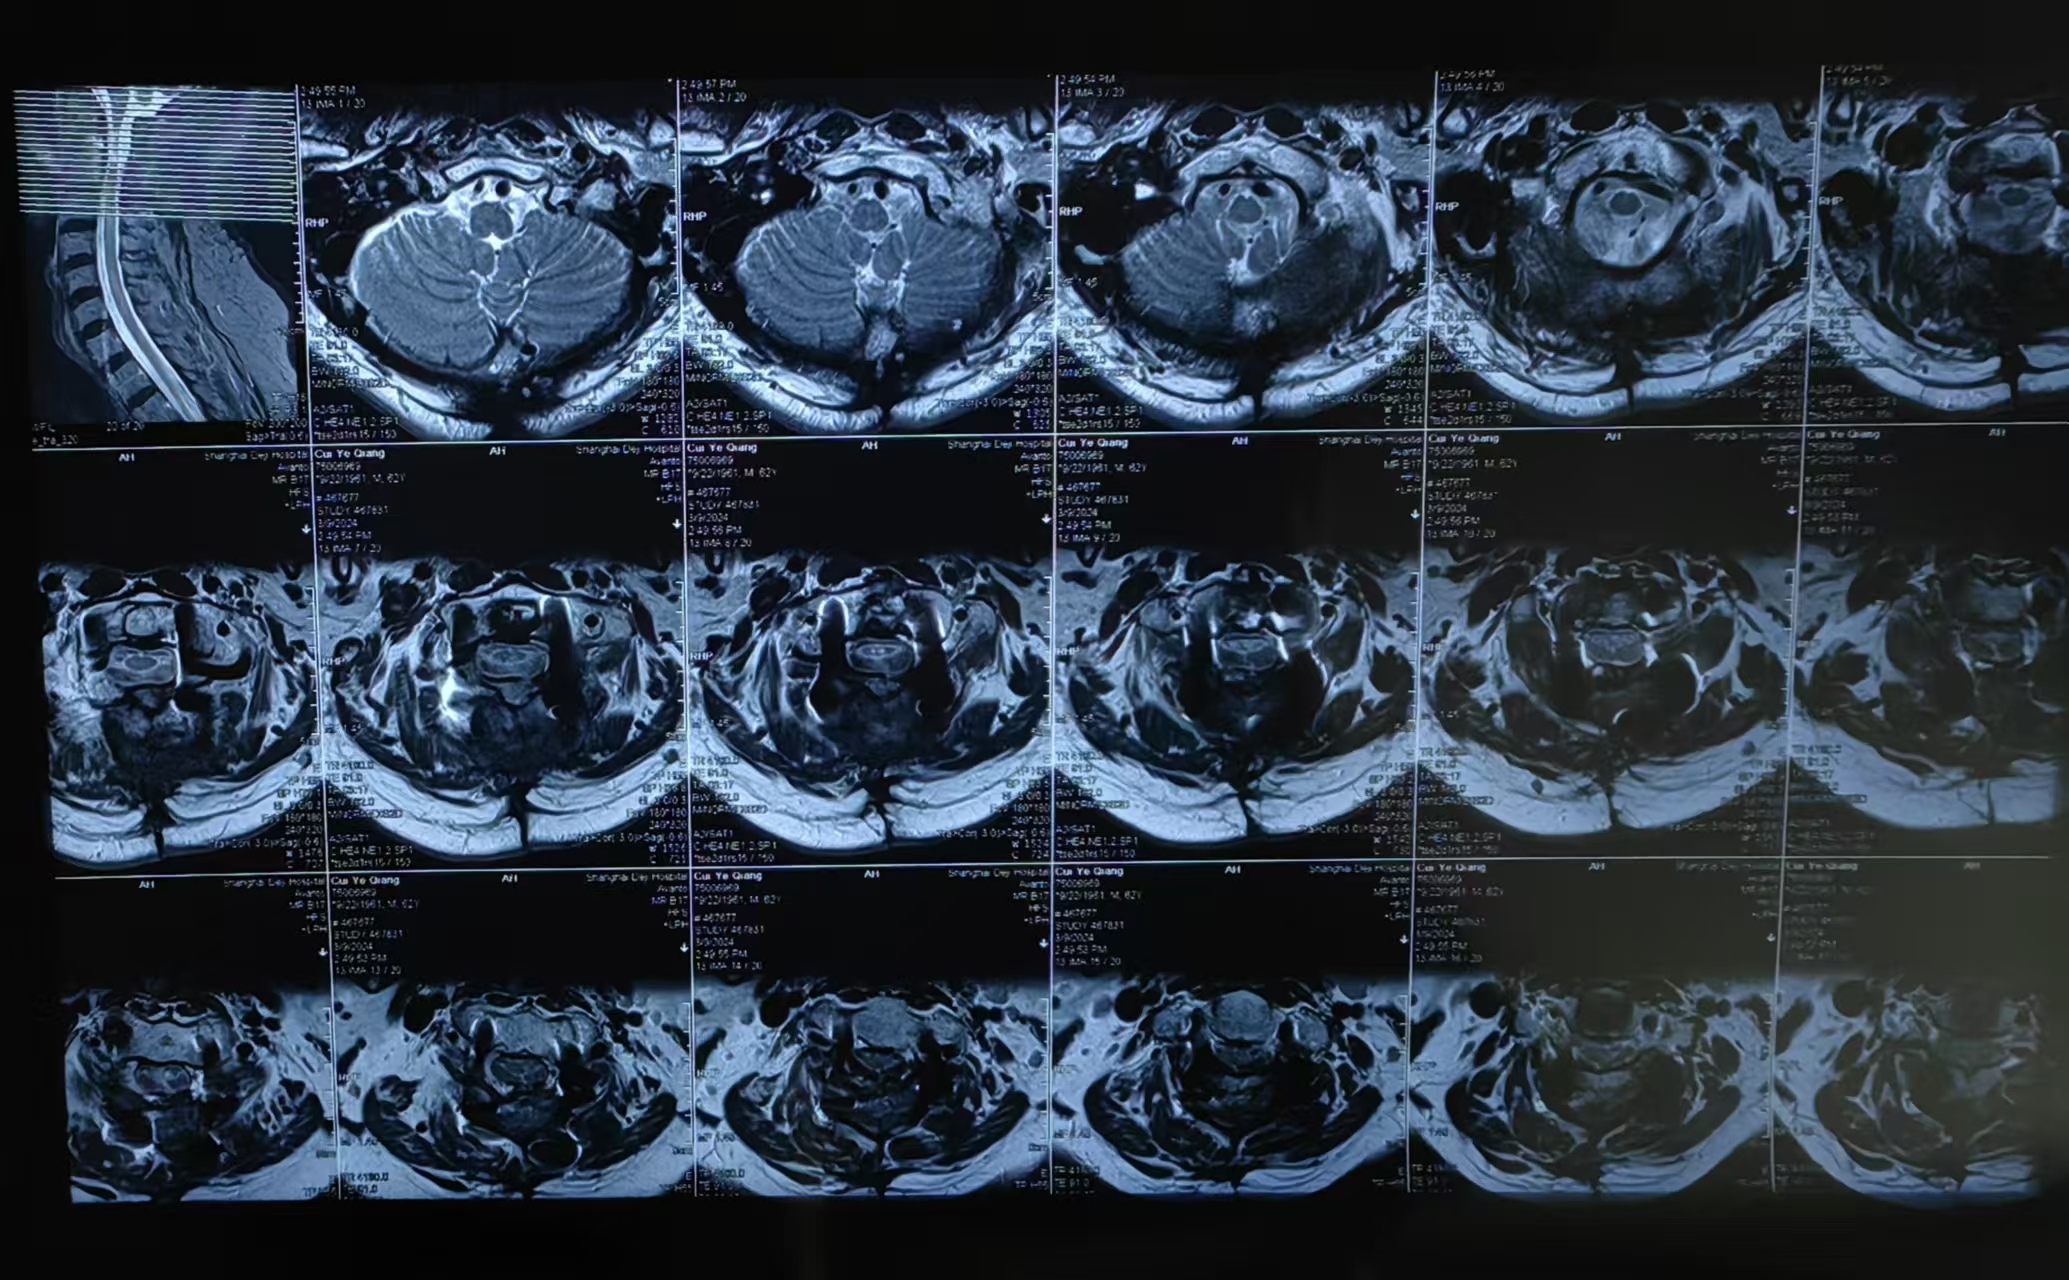

• 诊断:寰枢椎脱位,颅底凹陷

• 2023.09.01,复查,压迫脊髓。

• 2024.03.09,复查,对位良好,但术前症状难以恢复。